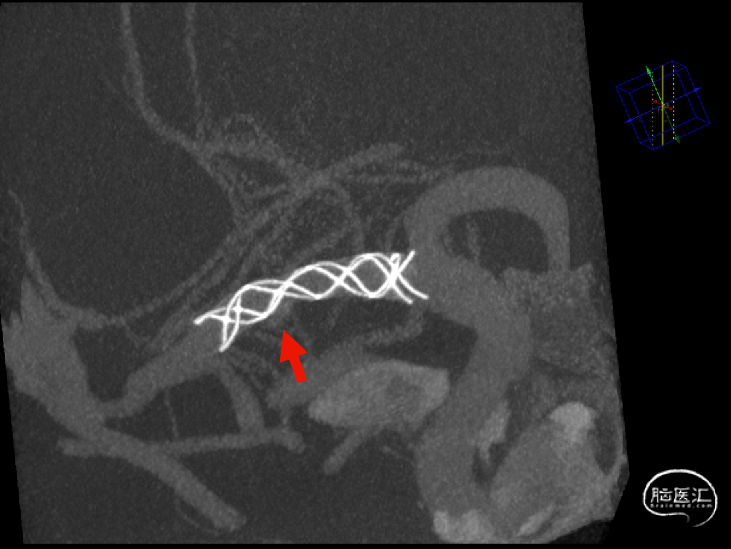

术后支架显影:定位精准,未覆盖颞前动脉及大脑前动脉。

强易达Choydar血流导向装置支架显影清晰,推送柔顺。

在弯道内支架轻松打开,不易扭结。

改良工艺提升镍钛支架的径向支撑力,贴壁良好。